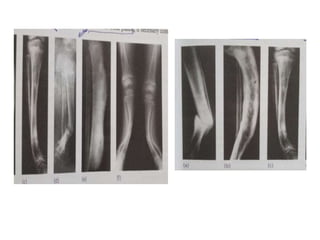

• BONES

Localized change - BENIGN TUMOURS – well defined , sclerotic

MALIGNANT TUMOUR - Ill defined areas , permeative

DIAGNOSTIC ASSOCIATIONS

– Infection / malignancy - Bone destruction + periosteal new bone

• BONES Shape Generalized change– bone density ( osteopenia/osteosclerosis) abnormal trabeculations ( Paget’s disease ) sclerotic /lytic lesions ( diffuse metastatic infiltration) Localized change - BENIGN TUMOURS – well defined , sclerotic margin, smooth periosteal reaction MALIGNANT TUMOUR - Ill defined areas , permeative bone destruction & speculated periosteal reactions

DIAGNOSTIC ASSOCIATIONS • Osteoarthritis-Narrowing of joint space+subchondral sclerosis +cyst – Inflammatory arthritis -Narrowing of joint space + osteoporosis + periarticular erosions – Infection / malignancy - Bone destruction + periosteal new bone formation